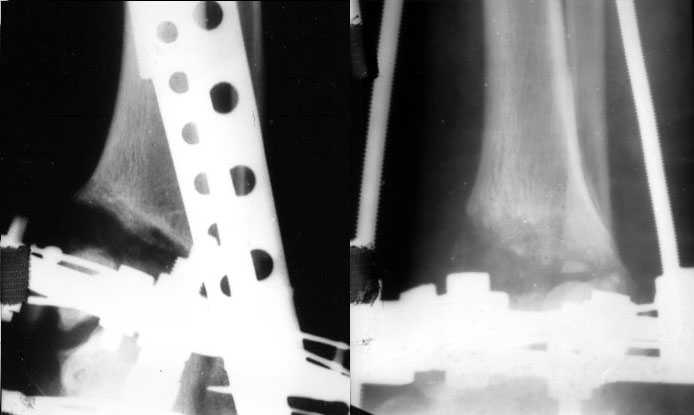

Перелом пилона сопровождается "компактированием метафиза" в дистальном отделе. Поэтому при фиксации переломов, после дистракции большеберцовой, очень важно провести замещение метафизарного "дефекта" костными или синтетическими заполнителями.

Без замещения дефектов из-за отсутствия опоры, переломы, со временем срастаясь, имеют тенденцию деформироватся в варус.

Медиальная подпорка "buttress technique" пластиной после пластики или хотя бы медиальная наружная фиксация более адекватны для удержания перелома, чем медиальные шурупы.

Из остеотомии предпочитительно, тактика "внеочаговой остеотомии".

Нежелательно остеотомию провести в очаге процесса, "несращения" нижней остеотомии часто встречается при реконструктивных операциях, поэтому немного выше, чем место сросшего перелома, где-то на уровне конца медиального шурупа (шурупы можно убрать), и еще с большим дистальным отрезком выгодно и удобно работать при манипуляции.

Для фиксации и восстановления высоты большеберцовой, подойдут гибридные аппараты внешней фиксации: классическая Илизаровская

компоновка, гексапод, аппарат Тэйлора, OrthFix, кто чем владеет и что имеет.

Для сохранения движения, проксимально и спереди стержни вместо спиц, потому что они менее травматичны для мышц и "не прошивают" их.